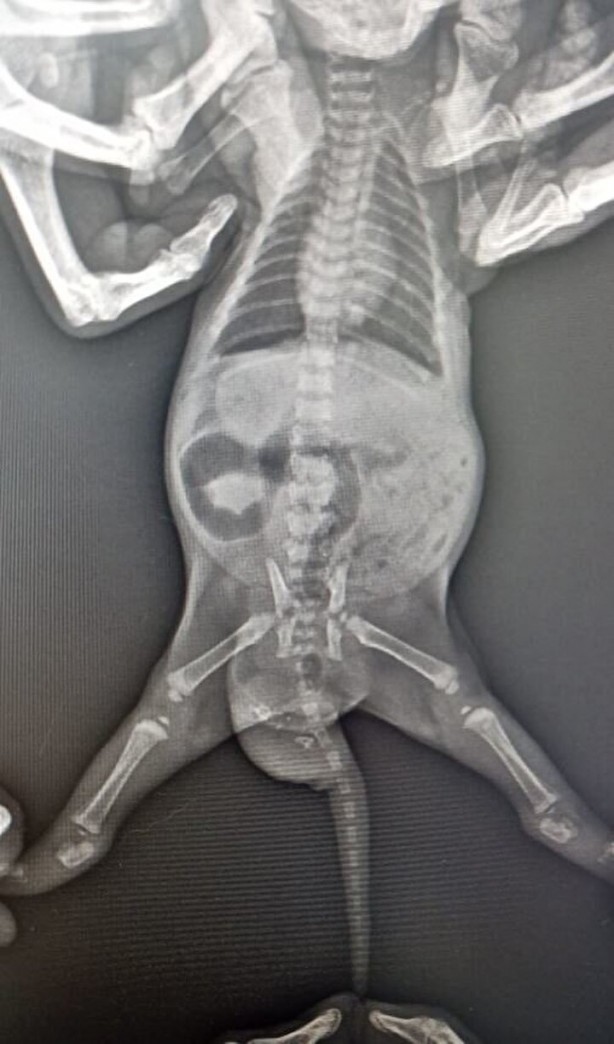

Doğan 2 yavru kediden birinin kuyruğunda şişlik olduğunu fark eden Yıldız, veterinere başvurdu. Veterinerde yapılan kontrolde kedinin kuyruğunda; dişleri, tüyleri, iskelet sistemi, kanal hücreleri oluşan yavru taşıdığı ortaya çıktı. Yavru kediye 'teratom' (canavar tümör) tanısı konuldu. Kedi cerrahi operasyona alınarak, tümör temizlendi. Şu an 4 aylık olan kedi, sağlığına kavuştu.

'DÜNYADA BİLİNEN İKİNCİ VAKA' Ameliyatı gerçekleştiren veteriner hekimlerden Emir Düzgören, kedi ile ilgili vaka bildirim raporu hazırlayacaklarını belirterek, "Yavruyu anesteziye uygun hale geldiğinde röntgene aldık ve içeride kemik benzeri dokular olduğu tespit edildi. Ardından çocuğun kuyruğunun alt bölümüne teratom tanısı konuldu. Çoğalan hücrelerden birinin bir tümör hücresine dönüşmesi sonucu oluşmuş. Bu çocukta hem deri, kıl, kemik, kanal hücrelerinin tamamı gelişen canavar tümör oluşmuş. Kardeşi gibi düşünebiliriz; ama tıbbi olarak aslında bir tümör.

Bilinen tek vaka bildirimi bizim dışımızda yurt dışında var. Vaka bildirim raporu hazırlayacağız, bunu bilimsel dergilere göndereceğiz. İkinci vakanın da gerçekleştiğini dünyadaki tüm veteriner camiası bilecek. Operasyon çok başarılı geçti. Diğer kardeşi ile aynı, operasyon izi dahi kalmadı. Çok heyecanlandık. Muhtemelen meslek hayatımızda bir daha böyle bir vakaya denk gelmeyeceğiz. Belki Türkiye'de bile bir daha böyle bir vaka olmayacak. Bize denk geldi" dedi.